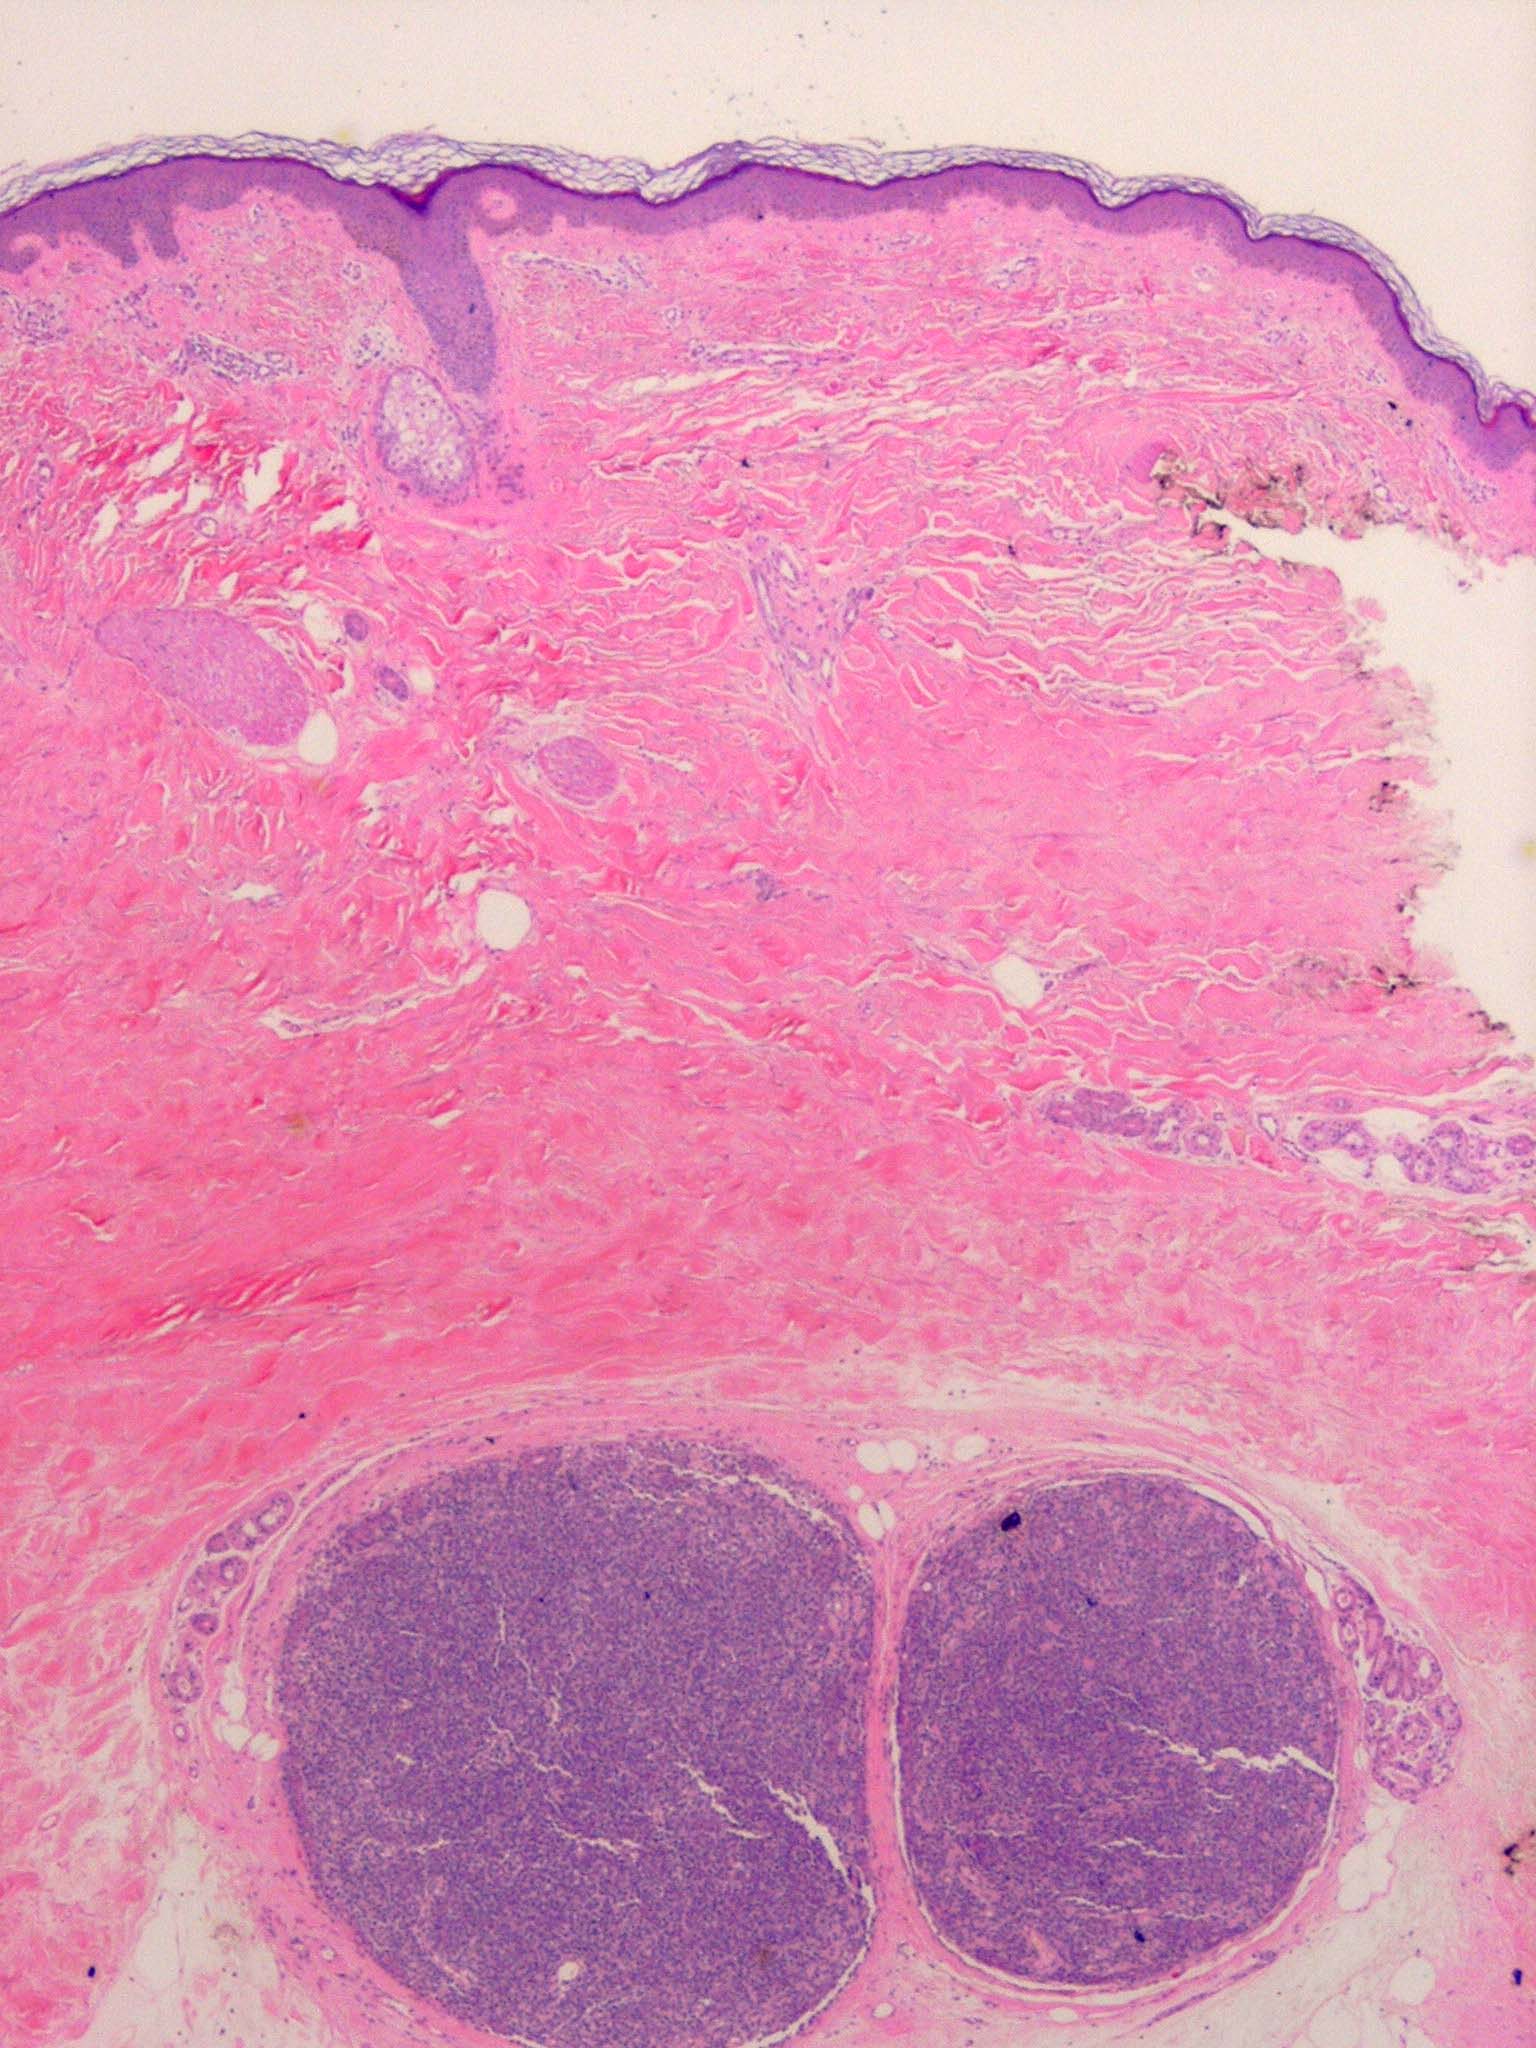

Spiradenoma=ورم غدي عرقي

OLYMPUS DIGITAL CAMERA